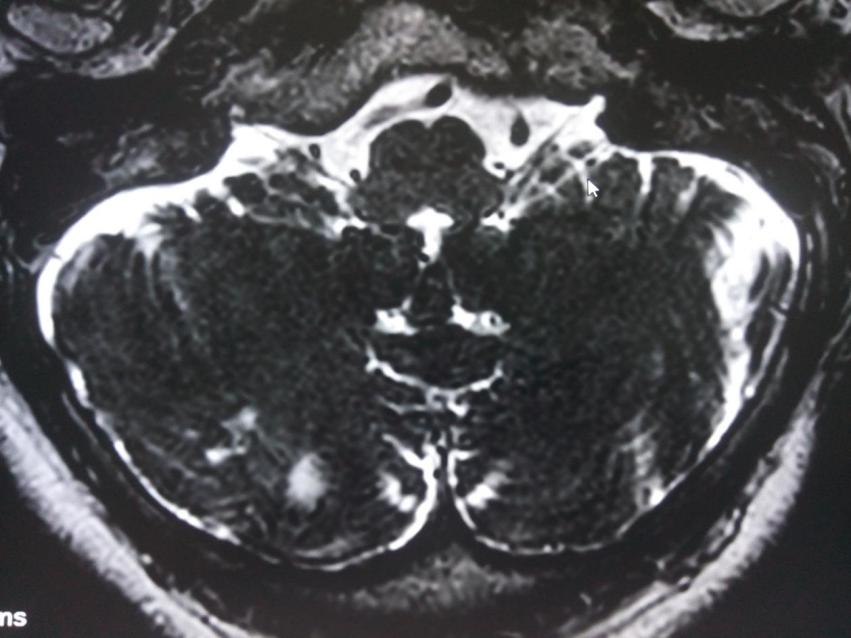

舌咽神經(jīng)MRTA檢查發(fā)現(xiàn)同側(cè)椎動(dòng)脈及小腦后下動(dòng)脈壓迫舌咽及迷走神經(jīng)